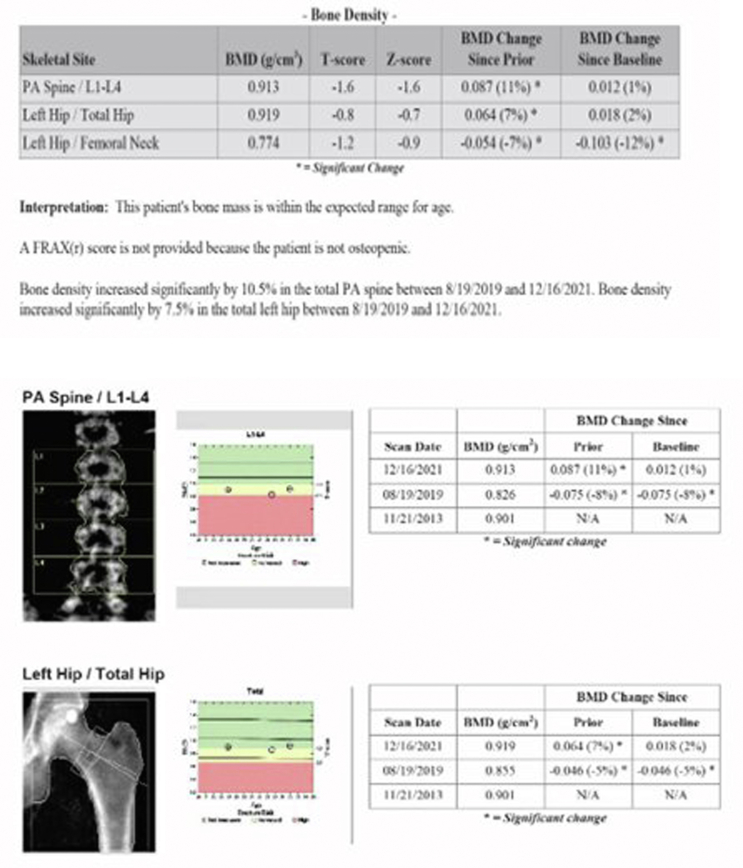

The patient was a 31-year-old man with history of CF who was referred to endocrinology clinic for the evaluation of hypogonadism. Serum testing revealed a total testosterone of 175 ng/mL (296-1377), luteinizing hormone 2.8 mIU/mL (1.2-8.6), and a prolactin of 341 ng/mL (3-13). A brain magnetic resonance imaging was obtained, which revealed a 1 cm hypoenhancing left sellar lesion. He was started on cabergoline. His testosterone increased to 707 ng/dL after a year on cabergoline treatment. His prolactin decreased to 12 ng/mL after a year of treatment. The pituitary adenoma decreased 50% in size 2 years after cabergoline was initiated.